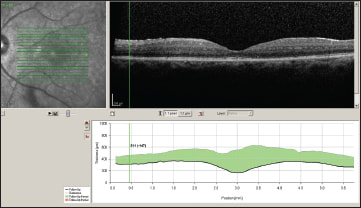

Two months after implant placement OS, the right eye was implanted. VA was 20/200 OD and 20/60 OS at that time. Four weeks after implantation OD, VA improved to 20/60 OD, and then to 20/40 OD eight weeks later (Figure 3). OCT nine months later showed dramatic resolution of CME (Figure 4). The pre-existing PSC cataract progressed. Phacoemulsification surgery with in-the-bag IOL implantation was performed OS 11 months after Retisert implantation in that eye. Vision improved from 20/80 to 20/50 after the surgery.

Figure 4. OCT of the left eye (upper image) and right eye (lower image) 14 months after initial presentation.